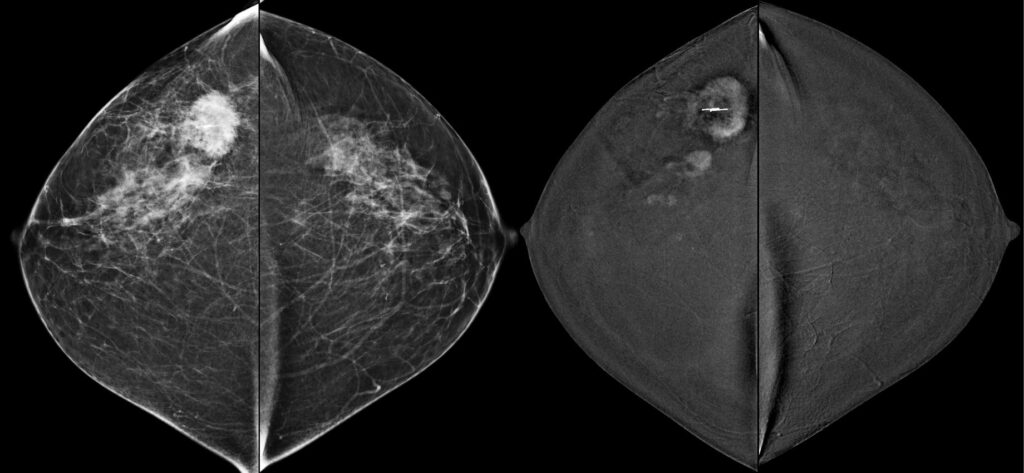

Mammografia con mezzo di contrasto (CEM)

Cos’è la Mammografia con Mezzo di Contrasto? La mammografia con mezzo di contrasto (CEM, Contrast-Enhanced Mammography) è un’evoluzione della mammografia tradizionale che utilizza un mezzo